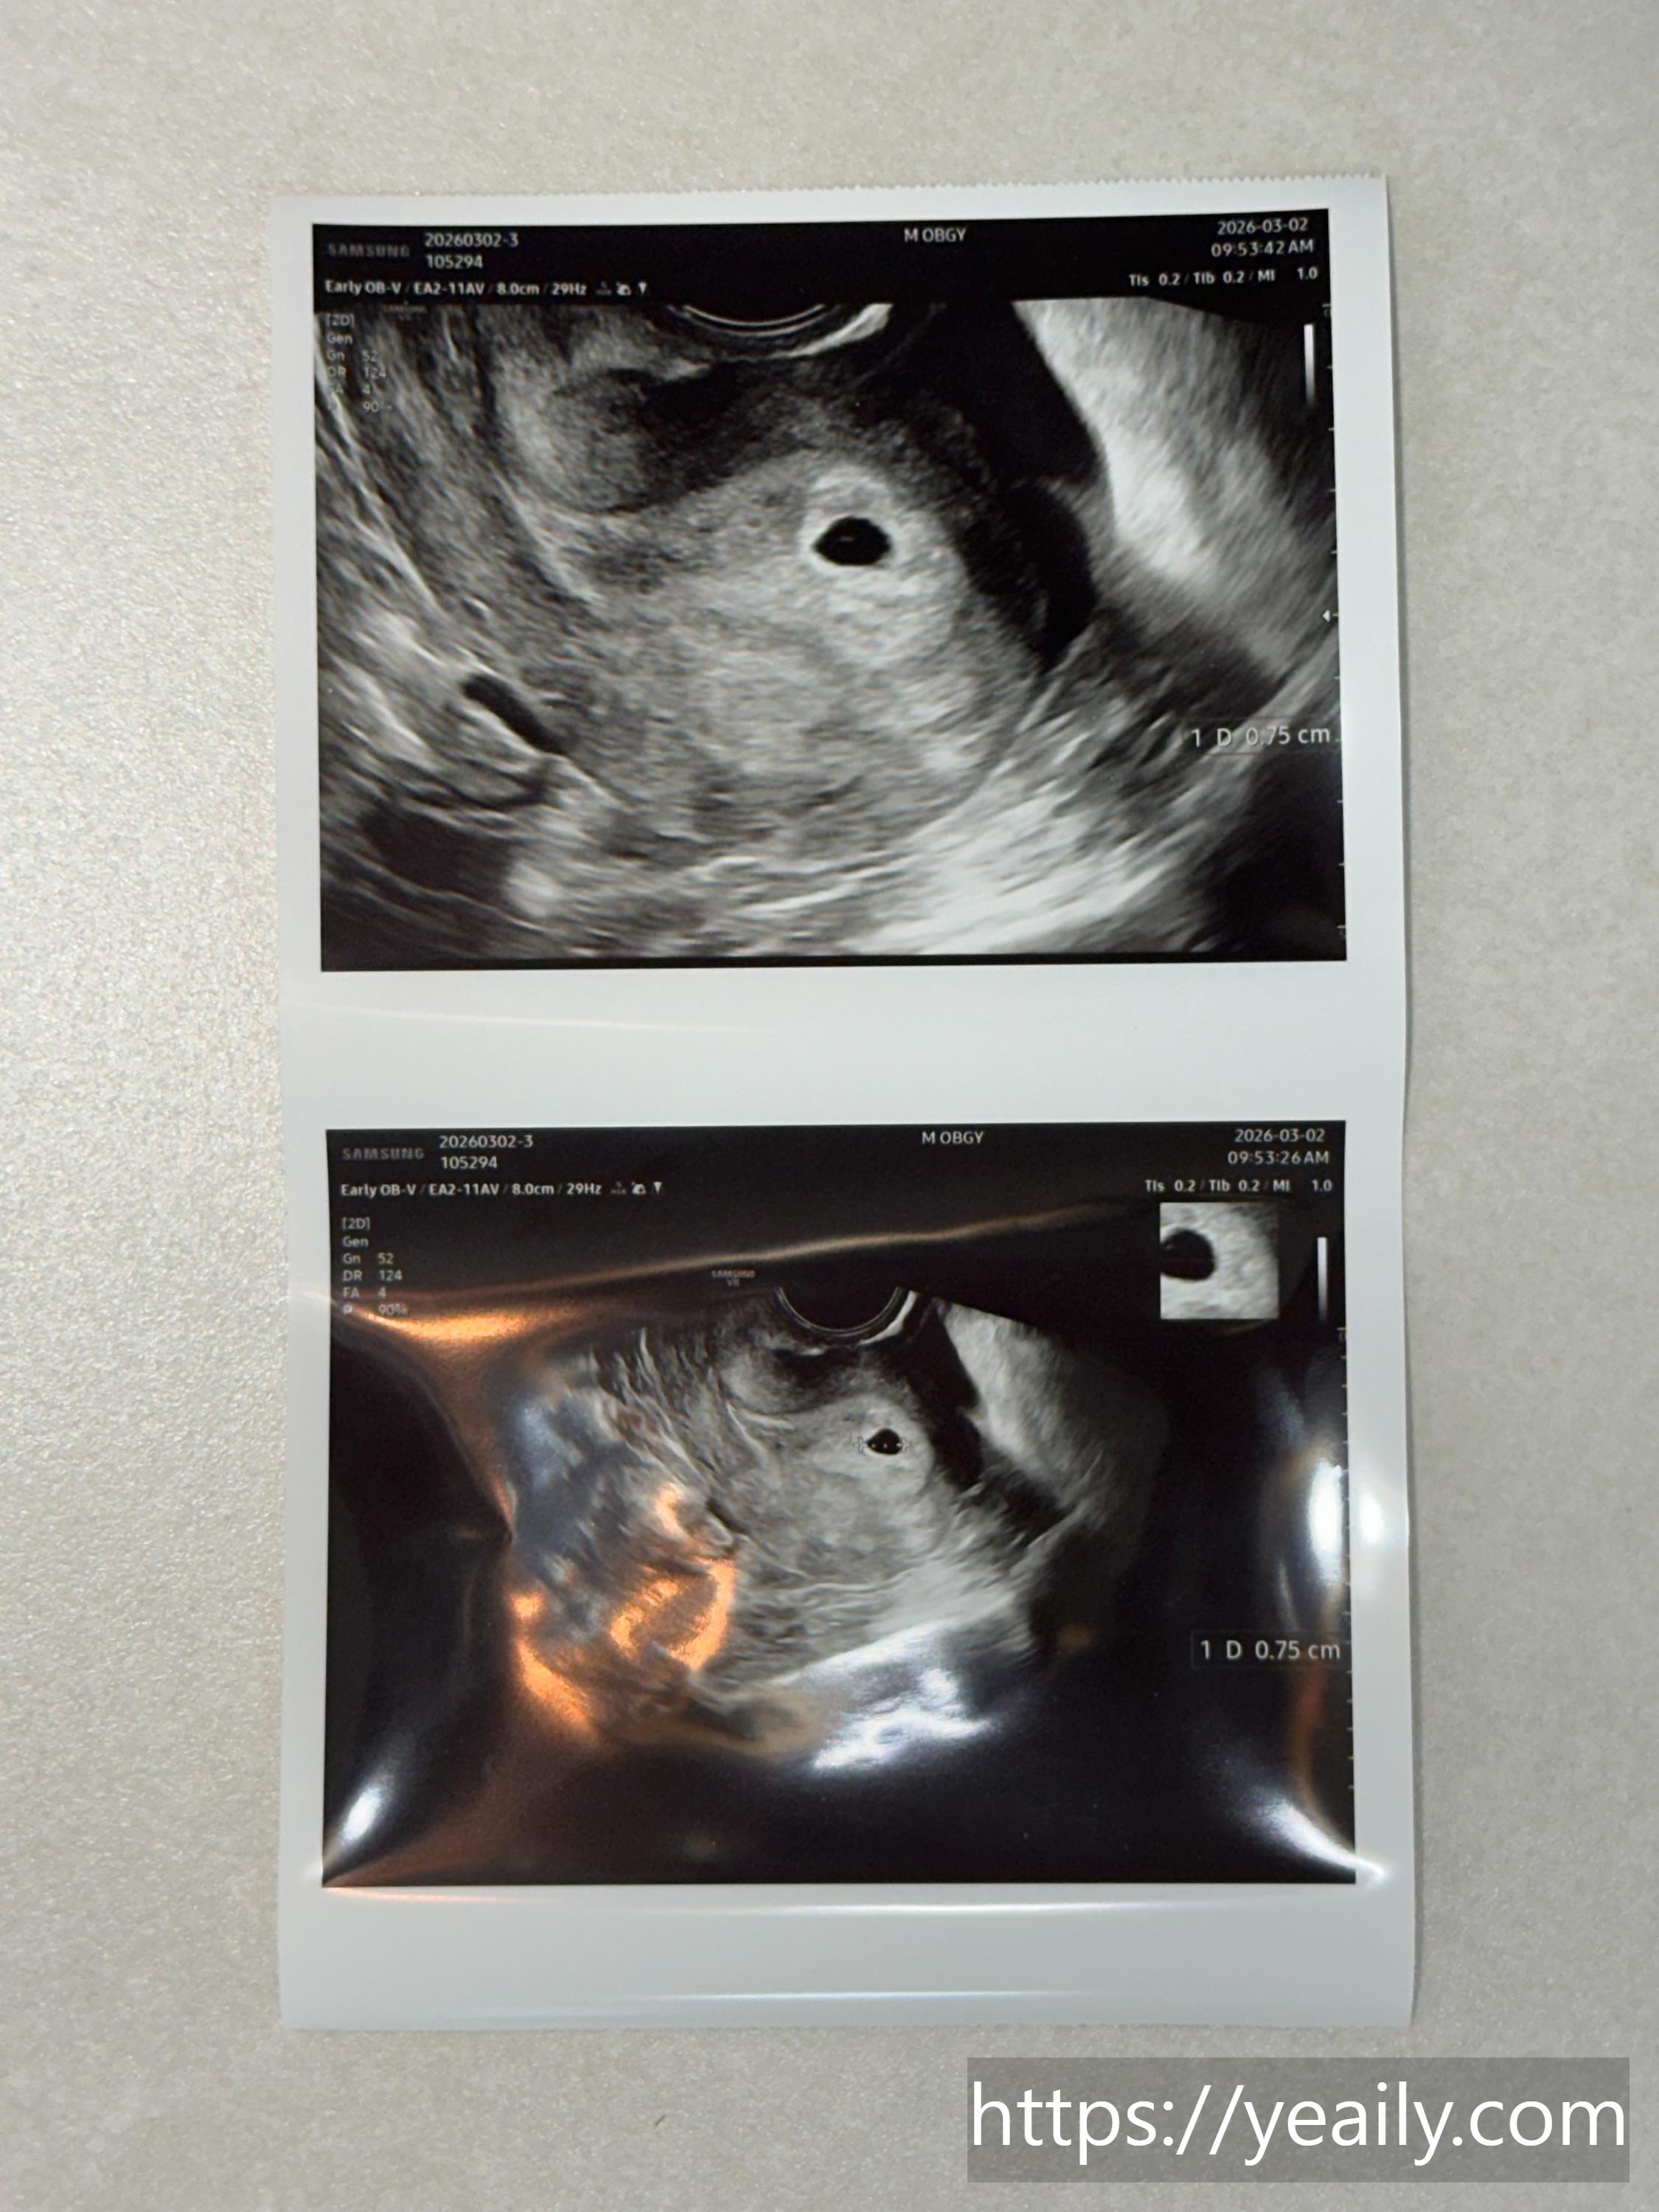

다시 병원을 찾은 날, 평소 정상이었던 혈압이 140이 넘을 정도로 긴장했나 봅니다. 다행히 초음파 화면에 7mm의 아주 작은 아기집이 나타났을 때, 그 신비로움은 이루 말할 수 없었습니다. 비록 아기 형태도 보이지 않는 점 하나였지만, 내가 지켜야 할 소중한 존재라는 생각에 뭉클해졌습니다.